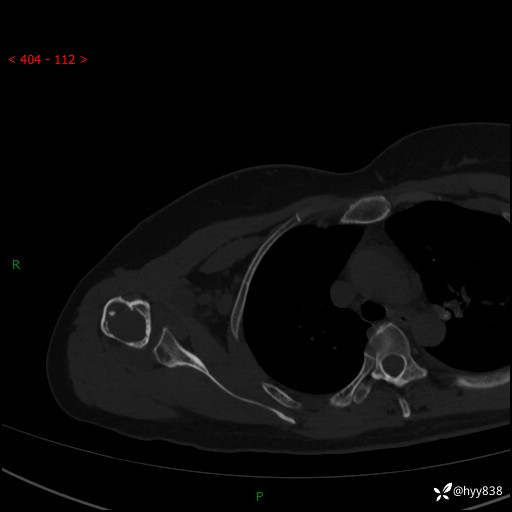

右肩关节CT平扫